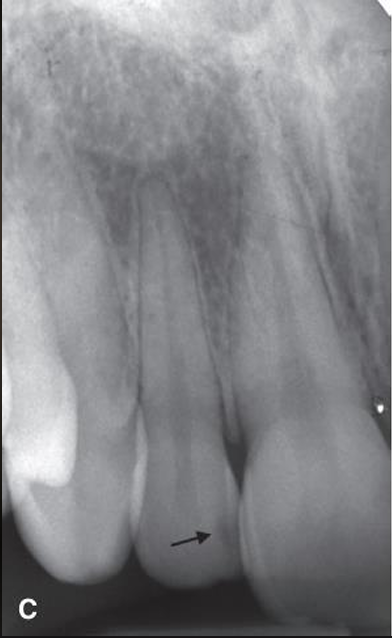

what are the arrows pointing to?

incipient interproximal caries